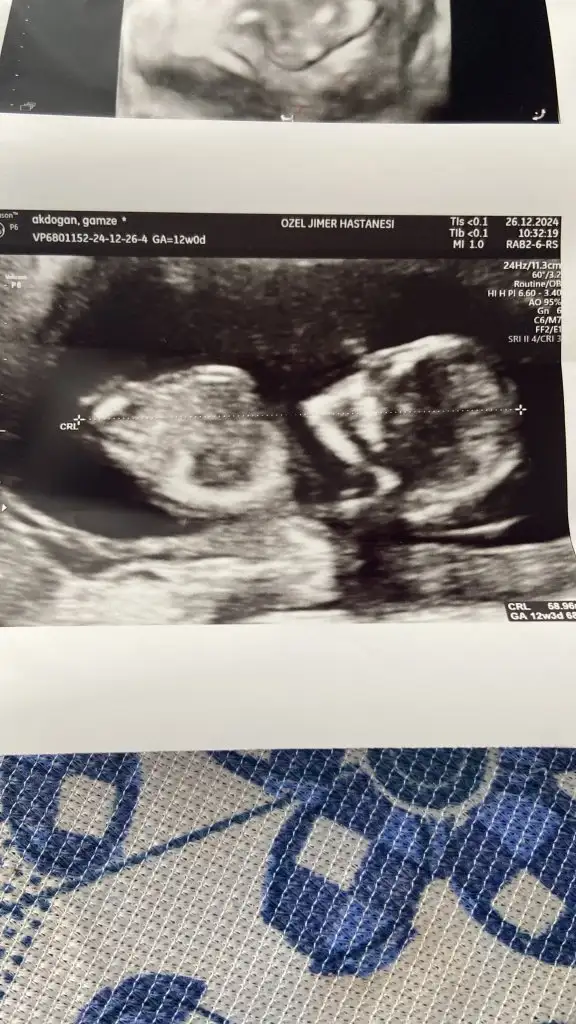

dr soylemeden siz gorun genital nub teorisi ( bebegin cinsiyeti)

12 haftalık cinsiyet tahmini yapabilir msiiniz

Merhaba sizce cinsiyeti ne arkadaşlar nubu paralel kız gibi ama sanki yüz üstü uzanmış o yüzden kafam karıştı